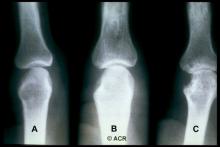

Top 5 and Bottom 5 Joints

If you’re going to spend 10-20% of your clinic hours examining and caring for 28 or 68 or 360 joints – it may be instructive to own up to those joints we excel at and take note of the ones we avoid, despise or struggle with.